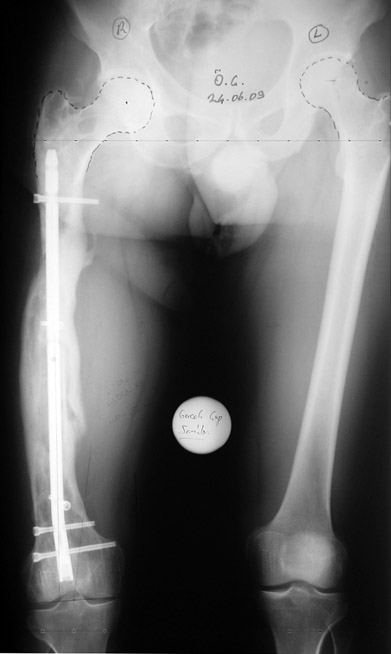

Appropriate radical debridement necessitates excision of all necrotic bone and soft tissues, and frequently causes instability at the involved extremity. The remaining bone and soft tissue defect has to be fixed and reconstructed. The distraction osteogenesis method of Ilizarov is used successfully for achievement of union, correction of the deformity, elimination of limb length inequality and reconstruction of segmental bone defects.

The duration of external fixation (external fixation index) depends on the amount of distraction required, and the extremity is prone to complications during this period. After the distraction phase is completed, the external fixator remains in place during the consolidation phase, which lasts twice as long as the distraction phase; but this period is hardly tolerated. If the external fixator is removed before sufficient consolidation is achieved, fractures, deformity and shortness will be the result. In our department, ‘lenghthening over nail’ method is used in order to decrease the external fixation index and increase patient comfort and activity level. In this method, the intramedullary nail is statically locked after the completion of the distraction phase, and external fixator is removed. The extremity is stabilized by the intramedullary nail during consolidation phase. In this way, complications due to long external fixation index or early removal of the external fixator are avoided.

Case 2